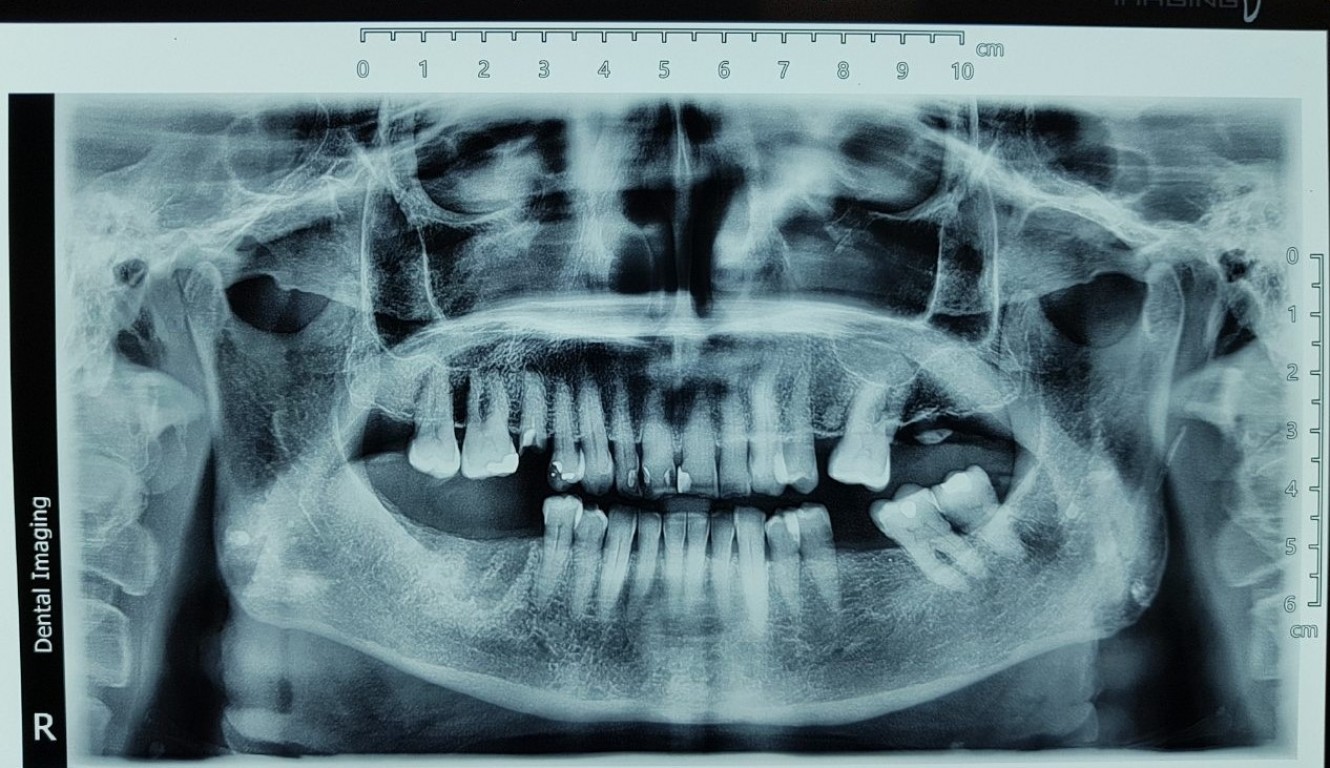

Implantswiss case by Dr. Aleksandar Radovanovic

Female, 69 years of age, Belgrade, Serbia Number of implants placed: 3 Type of implants placed: Implantswiss Bone level, 3.3 x 12 mm, 3.7 x 10 mm, 3.7 x 12 mm Bone type: D2 and D3